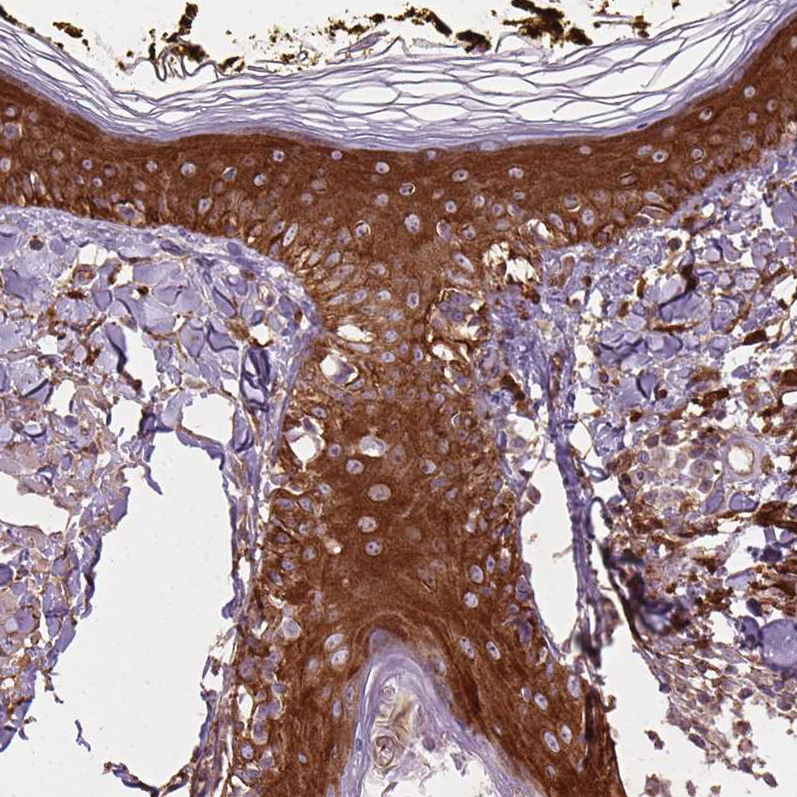

Immunohistochemical staining of human placenta shows moderate membranous/cytoplasmic membranous positivity in trophoblastic cells.